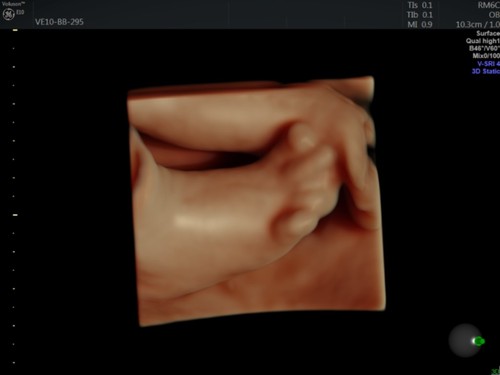

Другой снимок беременности двойней на сроке 8,5 недель.Сегодня одним из самых современных воплощений технологии являются ультразвуковые аппараты 4D. С их помощью можно долгое время наблюдать за плодом в животе матери с потрясающей четкостью в трех измерениях. «Раньше вы могли видеть только плоское двухмерное изображение плода в профиль, — говорит Барбара Дель Принс (Barbara Del Prince), главный управляющий директор по ультразвуковой продукции компании GE Healthcare. — Но сегодня вы можете наблюдать за его движениями в режиме 3D, видеть его улыбку или гримасу, рассмотреть его индивидуальные особенности».

Снимок плода в возрасте 28 недель, полученный в приложении HDlive Flow.

Снимок плода в возрасте 28 недель, полученный в приложении HDlive Flow.Данная система совместима и с новым программным обеспечением HDlive Silhouette, которое позволяет делать реалистичные снимки со всеми анатомическими подробностями. Медики могут использовать ее для изучения как внутренних, так и внешних органов, а также головного мозга, лица, рук и ног плода. Подобное изучение особенно важно в первом триместре беременности.